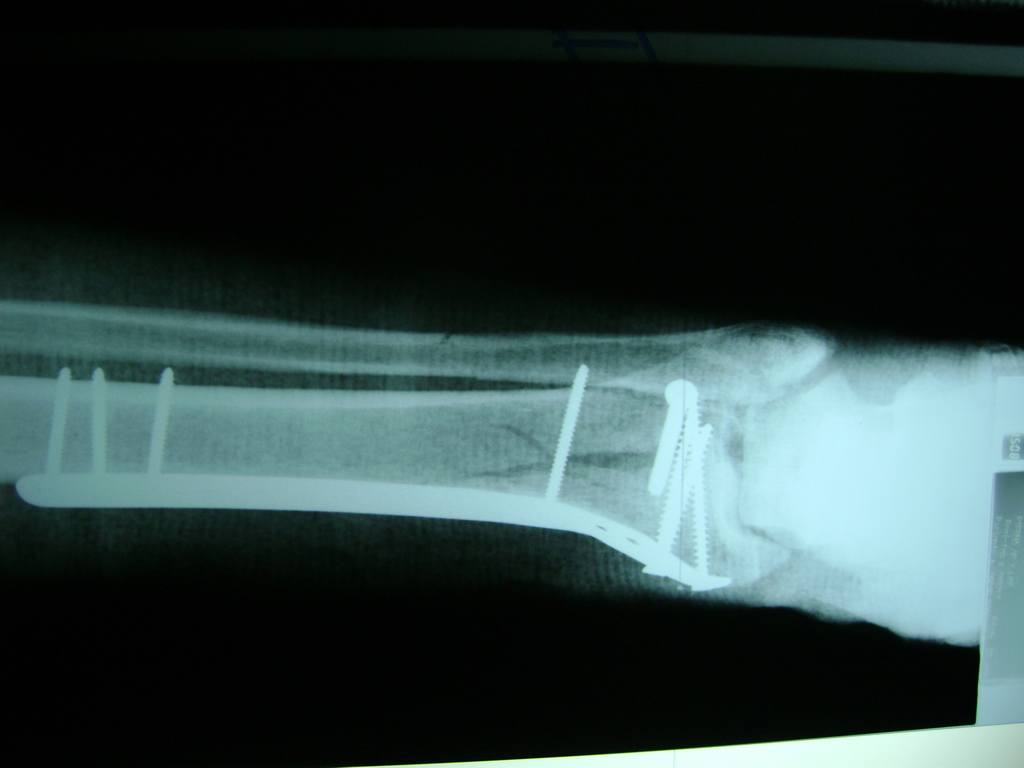

Cirugías

Aunque cada uno de estos huesos puede fracturarse por separado, normalmente la rotura es una lesión que se produce de forma conjunta

La mayor parte de las roturas implican a la parte proximal del hueso (parte del hueso próximo a la rodilla) o a la parte distal (parte del hueso cerca del tobillo).

Debido a la fina cobertura de piel que recubre la tibia y el peroné, las fracturas generalmente son abiertas, es decir, el hueso roto rasga la piel, atravesándola. Las fracturas de tibia y peroné generalmente se producen por un fuerte impacto o torsión.